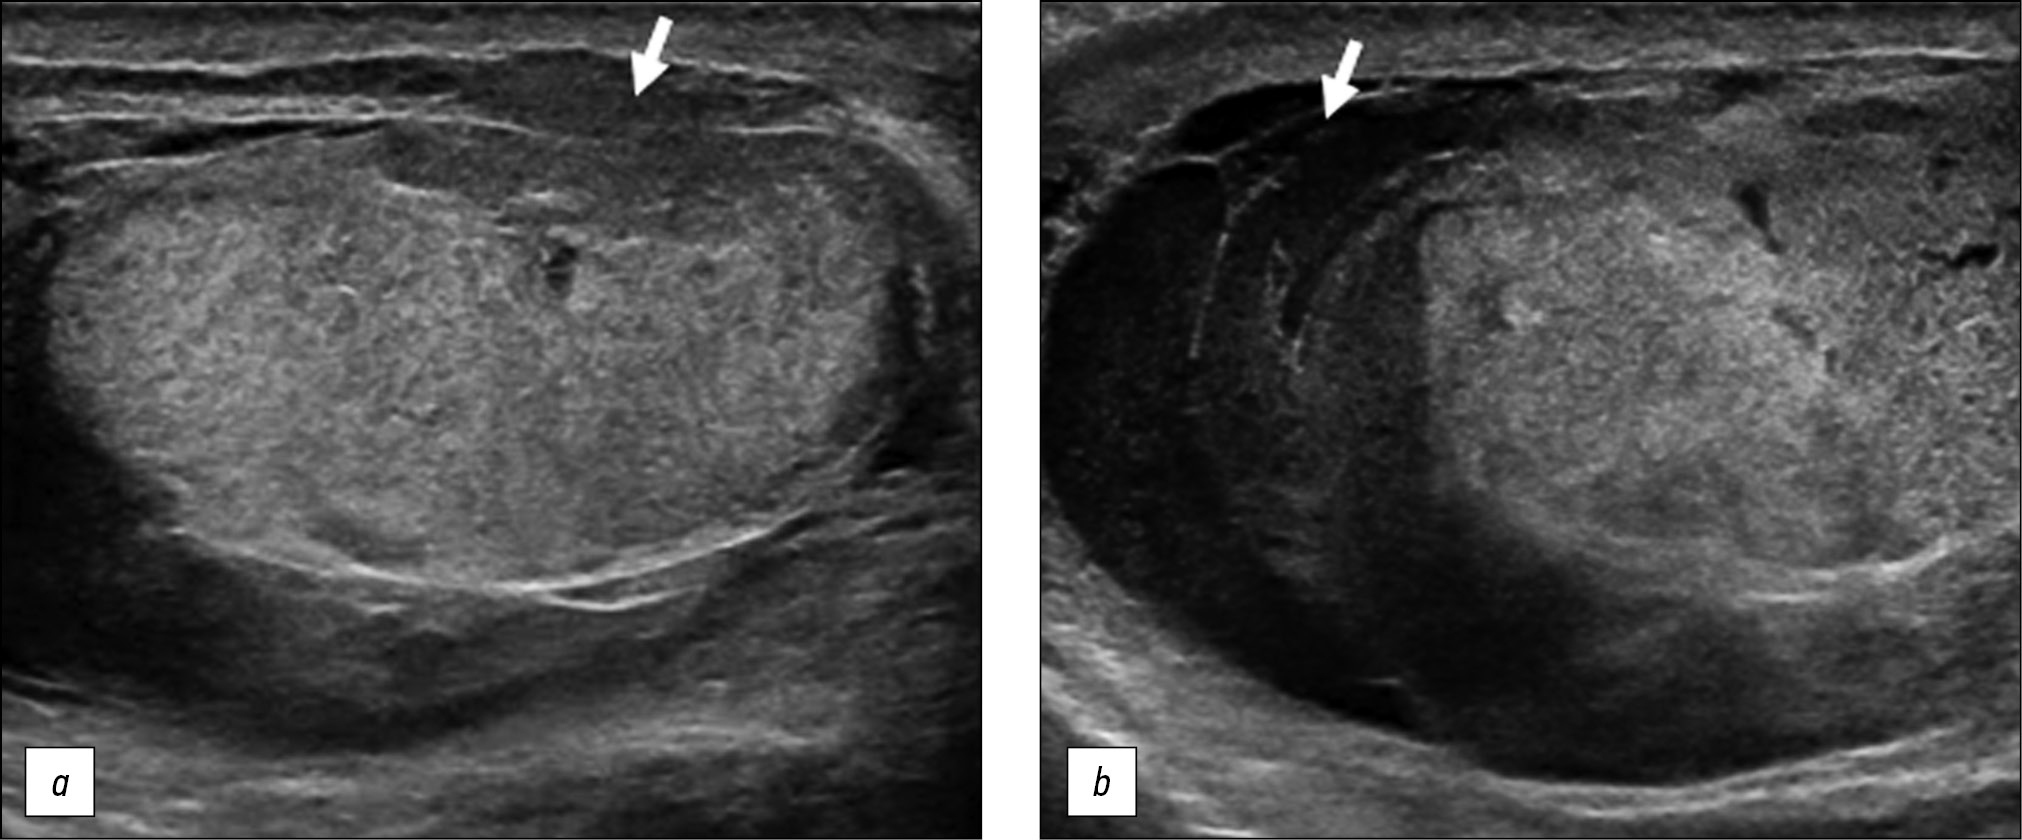

A healthy 15-year-old male teen was hit in the scrotum with a kick in the groin during a football match. He had an immediate and severe pain. After a few hours, although symptoms had improved, he presented to our emergency department with persistent swelling and purplish discoloration of the left scrotum. He did not report any other injuries. The genitourinary examination revealed that the left hemiscrotum was about two times larger than the right with severe ecchymosis. The left testicle was difficult to palpate because of pain and swelling, whereas the right testicle had a normal size and did not reveal any palpable abnormalities. The cremasteric reflex was not elicited on the left side. Scrotal ultrasonography (US) showed moderate scrotal edema and hematocele with a discontinuity in the tunica albuginea characterized by an abnormal contour (Figure 1). Color Doppler US (CDUS) documented a loss of vascularization in the upper pole that extruded into the broken portion of the testicle of approximately 2.5 cm (Figure 2) but no evidence of torsion or infarction. Urology consultation was requested, and a contrast-enhanced US (CEUS) was performed, which confirmed the diagnosis of testicular rupture and determined the amount of the vital parenchyma (Figure 3). The patient was hospitalized for urgent examination of the left hemiscotum based on the US results. During surgery, a large hematocele was evacuated, and a closer inspection of the testicle revealed a lesion of the tunica albuginea. Primary closure of the tunica was performed (Figure 4). The patient made an uneventful recovery, and he was discharged after 4 days.

Figure 1. B-mode ultrasonography images. (a) Interruption of the tunica albuginea with the protrusion of echogenic material (arrow) that represents an index of breaking. (b) Hematocele of moderate size (arrow) and a heterogeneous appearance of testicular parenchyma, attributable to an intratesticular contusion.